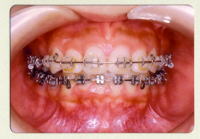

使用する装置

目立ちにくいセラミックブラケットを使用します。

咬み合せの状態によっては、下の歯にメタルブラケットを使用します。